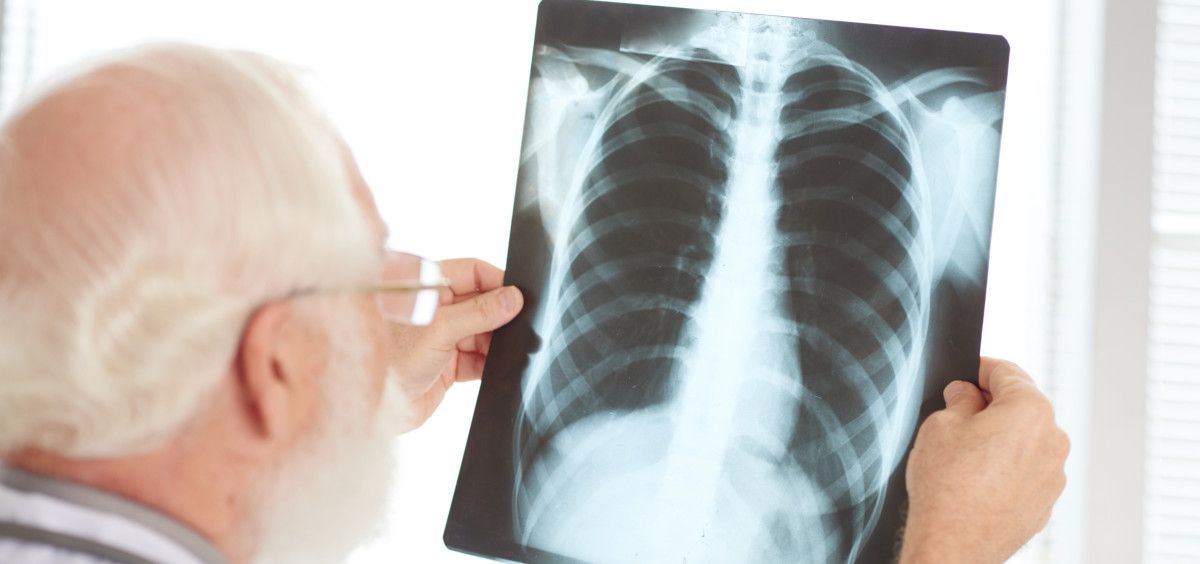

El pulmón es el órgano diana de la COVID-19. La neumonía bilateral aguda causada por la COVID y que lleva a los pacientes a urgencias supone un riesgo de intubación en el 25% de los casos, según la experiencia acumulada durante la primera y segunda ola en España. Una vez superada la fase más aguda de la enfermedad, todavía se desconoce qué pacientes van a desarrollar secuelas pulmonares intersticiales post-COVID-19, incluida la fibrosis pulmonar, y qué pacientes se van a recuperar.

Con este propósito, se recogerán los datos clínicos de los pacientes incluidos, se les tomará una muestra de suero y DNA y se les seguirá durante dos años. “El daño pulmonar agudo o DAD (daño alveolar difuso) no solo se produce en la COVID-19, también lo pueden causar otros virus como la gripe A, y las secuelas pulmonares pueden ser variables en función de la capacidad reparativa del huésped (predisposición genética, envejecimiento biológico), la severidad del daño inducido, complicaciones o tratamientos recibidos. Conocer los factores clínicos y los biomarcadores que influyen en ello es crucial para reducir el impacto de la COVID-19 a largo plazo”, añade la doctora.

“En este estudio en pacientes post-COVID-19, se analizarán datos clínicos, características iniciales y evolutivas, genética, y mediadores séricos, y se analizarán en función de si han desarrollado o no alteraciones intersticiales y, posteriormente, entre los que presentan alteraciones parenquimatosas, se diferenciarán aquellos que reparan-recuperan la función o estado previo a la infección de aquellos en los que los cambios quedan establecidos o incluso presentan progresión de la fibrosis pulmonar. La COVID-19 es una oportunidad para estudiar cómo se produce este daño pulmonar crónico después de un daño agudo”, destaca Molina.